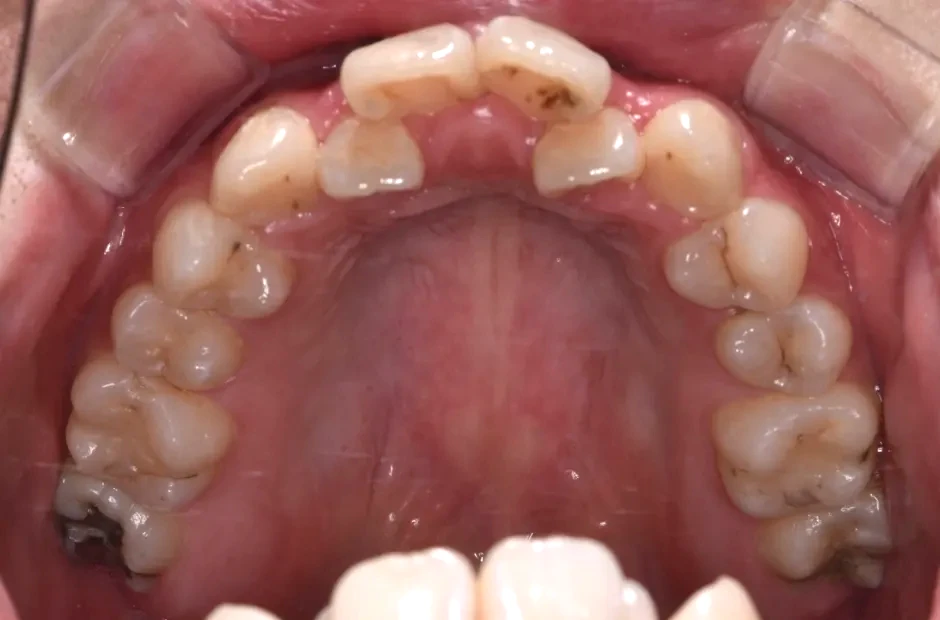

叢生

| 診断名・主訴 | 叢生 |

|---|---|

| 年齢・性別 | 43歳・女性 |

| 治療期間・回数 | 2年7か月 27回 |

| 治療に用いた主な装置 | 舌側矯正 |

| 抜歯部位 | 両顎4,4 |

| 治療費 | 100万円(税抜) |

| リスク・副作用 | 装置による違和感・疼痛・歯肉退縮・歯根吸収・虫歯のリスクなど |

治療前